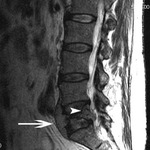

Magnetic resonance imaging of lymphoma: arrowhead indicates a soft-tissue mass protruding into the spinal canal. Arrow points to the tumor protruding anterior to the L5 vertebral body

Courtesy of Dr K. Singh; used with permission